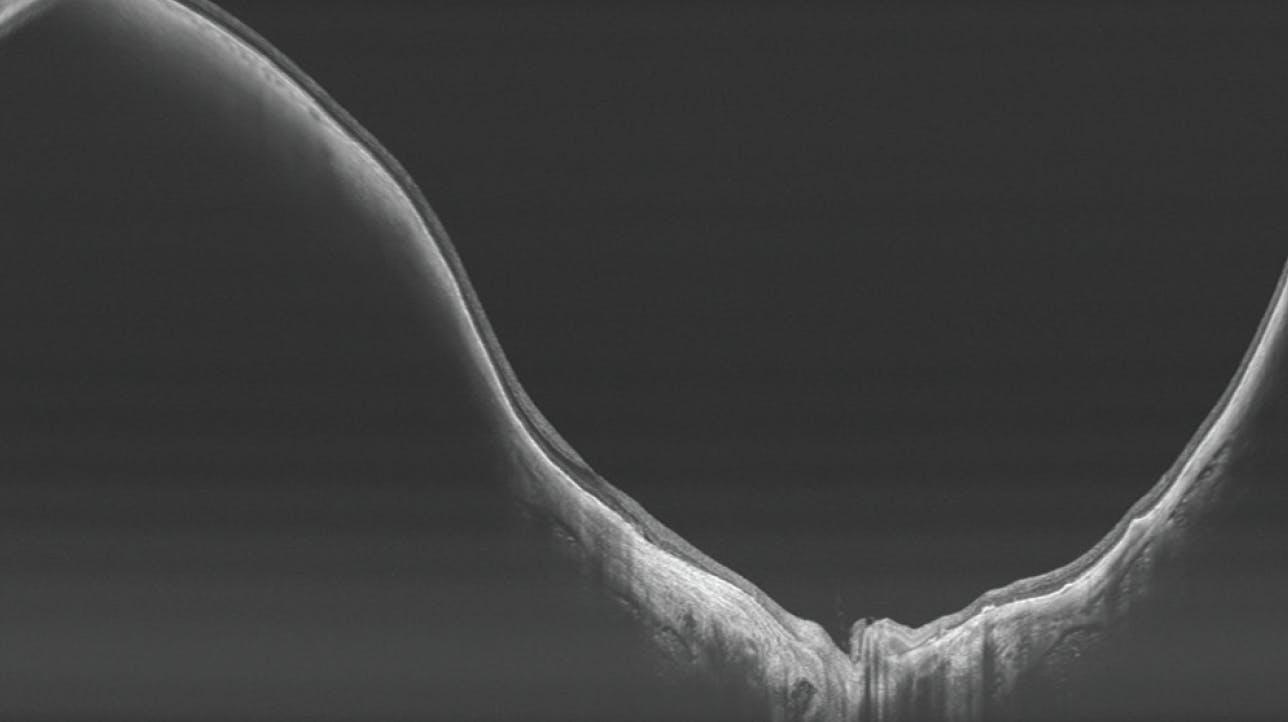

Beyond the detection of macular lesions in eyes with pathologic myopia, clinicians must remember the large spectrum of peripheral lesions in highly myopic eyes. Ultra-widefield color fundus photography and ultra-widefield OCT have been widely used in recent years for the detailed assessment of posterior staphylomas, a hallmark of pathologic myopia. While the initial 1977 classification of posterior staphylomas identified 10 different types of posterior staphyloma on fundus examination,12 there was no universally accepted definition. More recently, Ohno-Matsui et al used ultra-widefield color fundus photography and 3D MRI to visualize the entire extent of posterior staphylomas and critical features of staphyloma edges, such as gradual choroidal thinning from both sides, scleral inward protrusion, and posterior scleral displacement (Figures 5 and 6).13

<p>Figure 6. Ultra-widefield OCT of a highly myopic eye reveals a posterior staphyloma. Note the changes at the edge of the staphyloma with a gradual decrease of the choroid and the scleral protrusion.</p>

Figure 6. Ultra-widefield OCT of a highly myopic eye reveals a posterior staphyloma. Note the changes at the edge of the staphyloma with a gradual decrease of the choroid and the scleral protrusion.